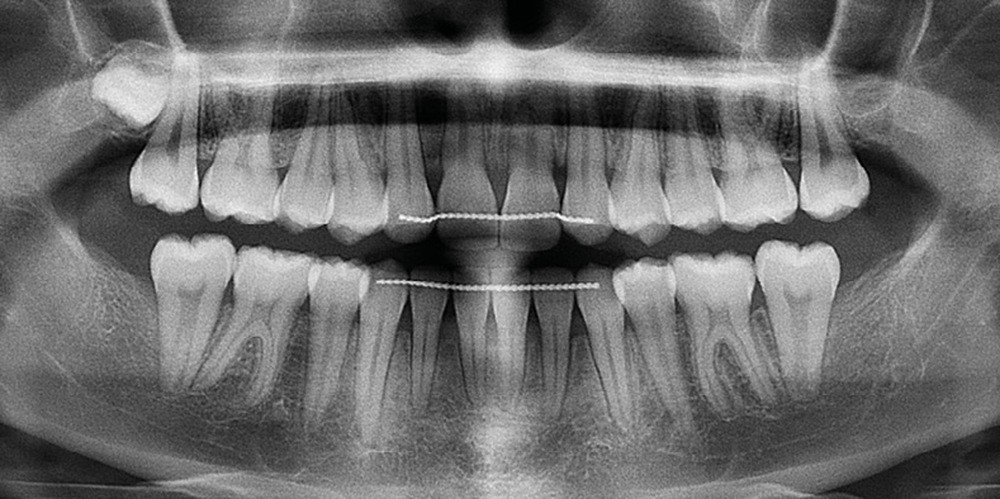

Les examens cliniques et radiologiques ont mis en évidence l’inclusion de 13 et 23, une légère classe II bilatérale par perte d’ancrage, un biotype parodontal de type IV de Maynard et Wilson avec une insertion du frein mandibulaire antérieur papillaire, une biproalvéolie et une typologie hypodivergente. La réalisation d’un examen tridimensionnel a permis de confirmer la localisation palatine de 23 et vestibulaire de 13 ainsi que de visualiser l’étendue des résorptions radiculaires touchant 12, 21 et 22 (fig. 1a-i).

Le plan de traitement choisi comprend les extractions de 63, 12, 22, 34 et 44. Ce choix s’est porté d’une part sur le fait de la présence de résorptions très avancées de 12 et 22 et d’autre part sur la correction de la biproalvéolie facilitée par l’extraction de 34 et 44 qui ont par ailleurs un diamètre légèrement inférieur à 35 et 45.

Un appareil multi-attaches .022 x .028 (prescription de Roth) est posé sur toute l’arcade mandibulaire et sur les secteurs postérieurs maxillaires (17 à 14 et 27 à 24) afin d’éviter au maximum la sollicitation de 11 et 21 et donc de limiter les résorptions radiculaires.